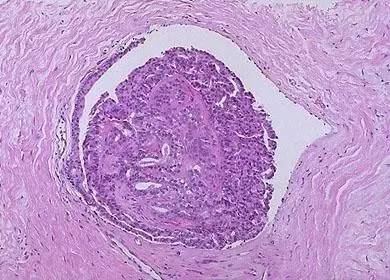

流行病学研究显示,肠道慢性炎症会增加结直肠癌的发病率。炎症性肠病,尤其是溃疡性结肠炎,已被认为是结直肠癌的易感因素之一。近年来,学者们关注到异常的肠道微生态是引起结直肠癌发生的重要因素之一,但具体原因有待阐明。

为刻画肠炎相关肿瘤发生中巨噬细胞的动态演变过程,研究人员构建出小鼠肠炎相关肿瘤模型,发现单核细胞样巨噬细胞特异性富集在肠炎相关肿瘤发生的早期阶段。单核细胞样巨噬细胞作为巨噬细胞的一个亚群,具有强分泌炎症性因子的作用,其数量改变对整体巨噬细胞的性质与功能影响深远。

相比于健康人群,溃疡性结肠炎、结直肠癌患者肠道中产脂多糖细菌增多;结合健康受试者、溃疡性结肠炎和肠炎相关结直肠肿瘤患者的转录组数据,研究人员进一步发现,免疫细胞与细菌产物的相互作用,构成了肿瘤内互作网络的核心。